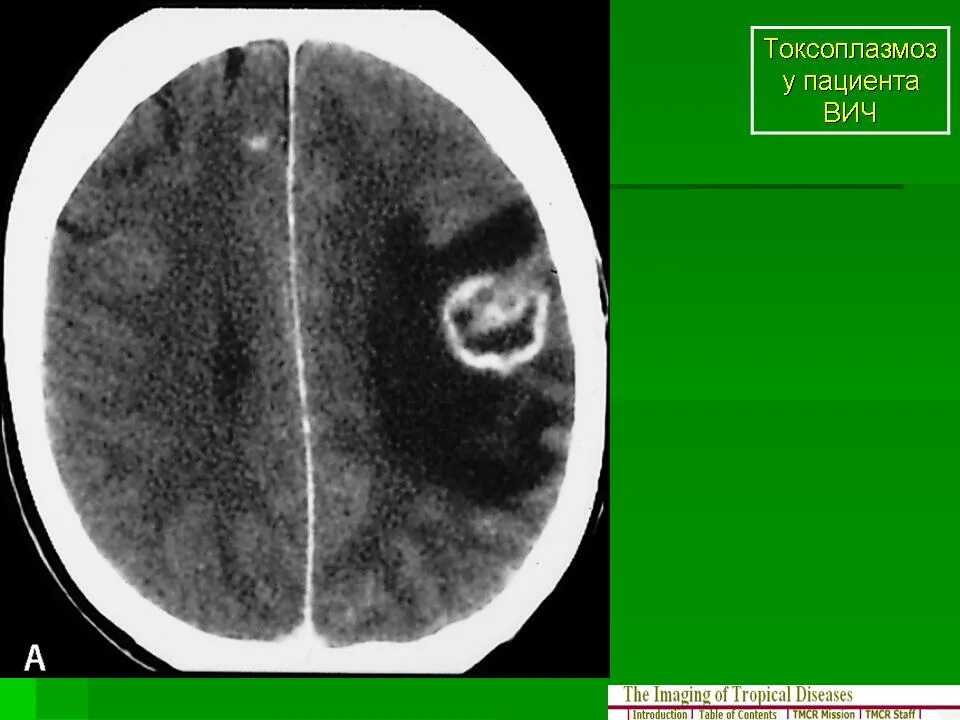

Токсоплазмоз у вич инфицированных